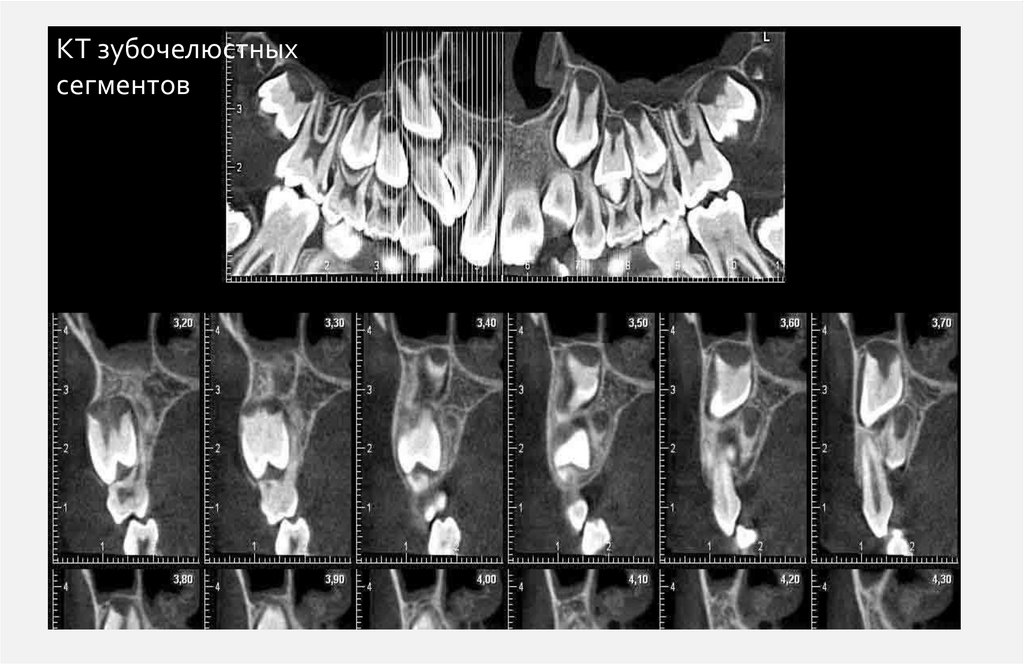

КТ зубочелюстных

сегментов